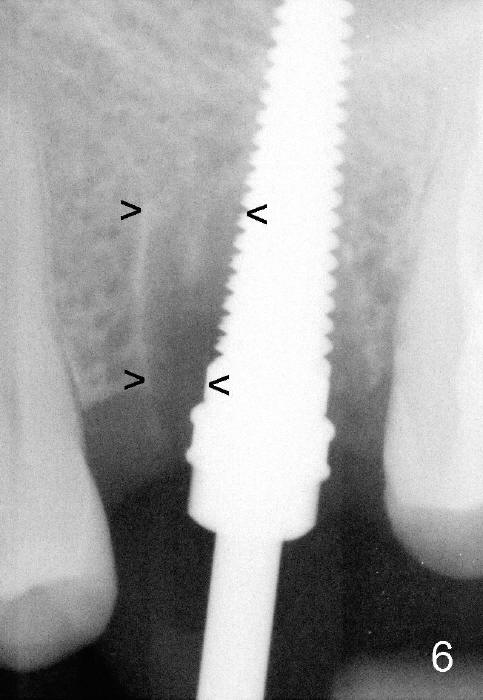

Fig.6 shows 4.5 mm tap in place with stability. It appears too high. When it is removed, the sinus membrane is found to have been perforated. The next taps (5,6 and 7 mm) are placed shorter by 3 mm with stability. A piece of collagen dressing and a small amount of bone graft (Fig.7 *) are inserted to the osteotomy before placement of a 7x14 mm implant.

Fig.8 illustrates the implant (blue) placed in the middle of the socket. The remaining buccal and lingual gaps (black) are then closed by graft and membrane. Placing the graft in the deeper portion of the mesiobuccal socket is not so easy because the large implant blocks the entrance (Fig.7 between lower arrowheads). If more graft has been dispensed and the earlier PA shows larger upper space exists (Fig.6 between upper arrowheads), the graft should be placed to that region prior to implant placement.